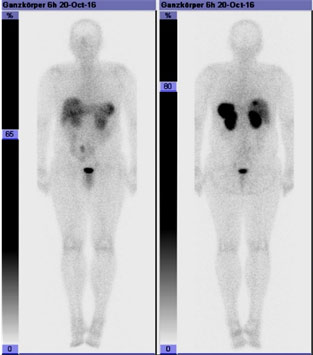

Somatostatin receptor scintigraphy

Images courtesy of: : Claraspital, Basel, Switzerland